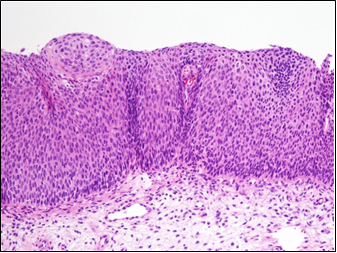

54세 여자가 건강검진의 자궁경부세포진 검사에서 비정형세포가 관찰되어 병원에 왔다. 질확대경검사에서 자궁 경부 1시 방향에 붉고 융기된 약 1 cm 크기의 병변이 보여 조직검사를 하였다. 현미경 소견이다. 원인은?

• 조직검사 결과는 미성숙 편평상피세포가 상피층 2/3 이상까지 확장한 고등급편평상피병터(High-grade SIL)를 시사한다. 이는 자궁경부암의 전단계로, 자궁경부에서의 지속적인 HPV 감염이 상피의 dysplasia를 유도한 상태이다.

• HPV는 자궁경부암과 100%에 가까운 연관성을 보인다.